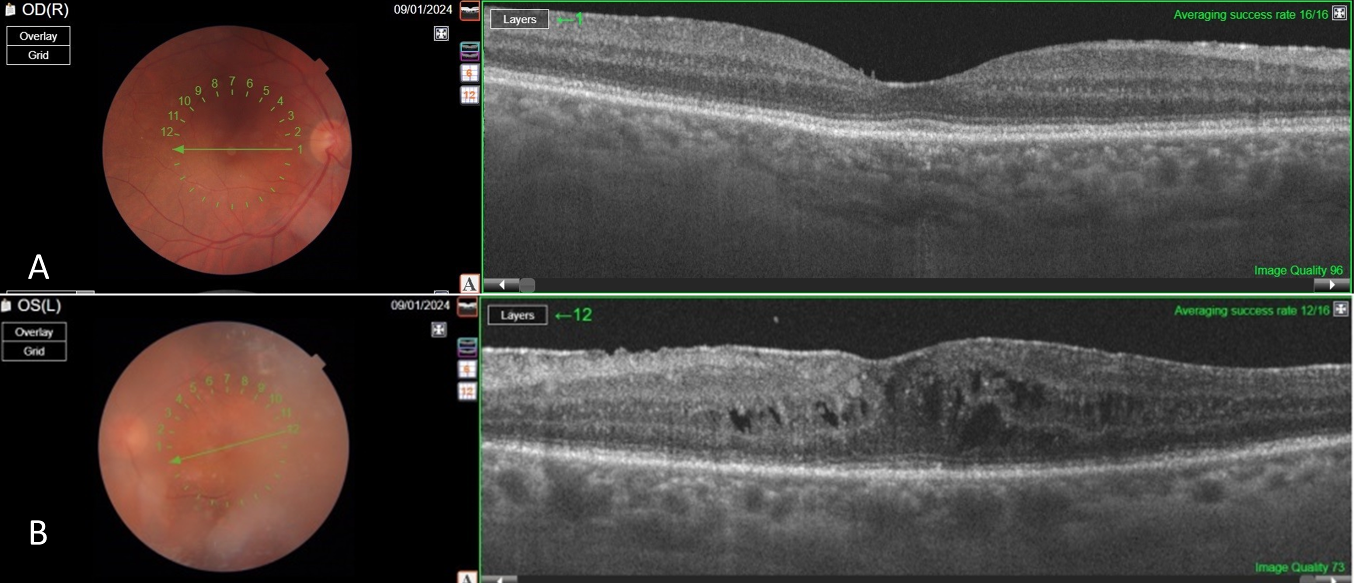

The patient completed R-CHOP protocol chemotherapy during the COVID-19 pandemic and underwent autologous stem cell transplantation, achieving systemic disease remission. However, the patient declined further treatment for brain and ocular involvement due to repeated COVID positivity and the challenges of treatment. At the 1.5-year follow-up, the right eye retained a visual acuity of 20/25, while the left eye was 20/125. Biomicroscopy showed quiet anterior segments in both eyes. However, the left eye exhibited residual +1 vitreous cells, cystoid macular edema, and an epiretinal membrane consistent with chronic inflammation (Figure 5 [Fig. 5]).

Figure 5: Post-treatment OCT images

The findings regressed in both eyes compared to the pre-treatment period (A–B). However, vitreous opacity and cystoid macular edema were observed, only in the left eye (B). Additionally, an epiretinal membrane induced by bilateral vitreous inflammation was noted (A–B)